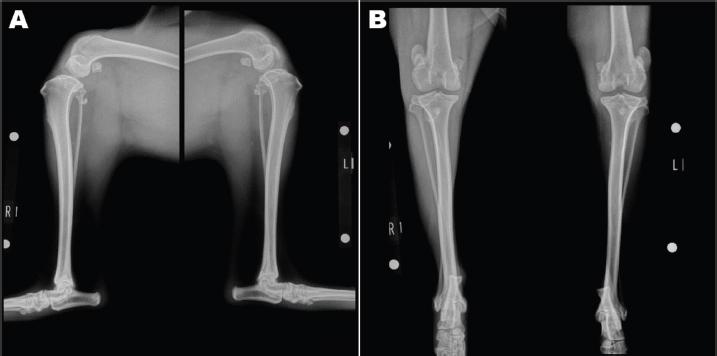

An 11-month-old intact male Siberian Husky was referred to us with the main complication reported as bilateral hind lameness and LPL, diagnosed by a family doctor. His posture showed an X-linked knee. Physiological examination showed bilateral patellar luxation with grade 4 and negative for cranial drawer sign and tibial compression test. The radiograph showed severe bilateral LPL without changes in the hip joint (Figs. 1A-B). His quadriceps (Q) angle showed right=43.37°and left=32.15°. Diazepam 0.1 mg/kg, ketamine 0.5 mg/kg, and fentanyl 5 μg/kg (intravenous), atropine 0.05 mg/kg (intramuscular), and meloxicam 0.2 mg/kg (subcutaneous) were administered as the premedication. After an induction of propofol 6 mg/kg, ropivacaine 0.22 mg/kg was used for epidural anesthesia. Under general anesthesia, the patient was immobilized in the supine position. Surgical techniques included bilateral block trochleoplasty, tibial tuberosity with tension band wiring using Kirschner wire, modified capsules (release of the lateral capsule and suturing of vastus medialis, plication), and the modified MPFL. The modified MPFL was used with the Cruciate Needle (medium, 40 lb) 40# suture (monofilament nylon) single strand (SECUROS, MA), suturing from the lateral aspect of the patella periosteum to the medial sesamoid bone (Figs. 2A-B). The postoperative radiograph is shown in Figures 3A-B. The patient has shown no luxation over 1 year after the operation.

Fig. 1. Preoperative radiograph. Severe bilateral LPL was detected.